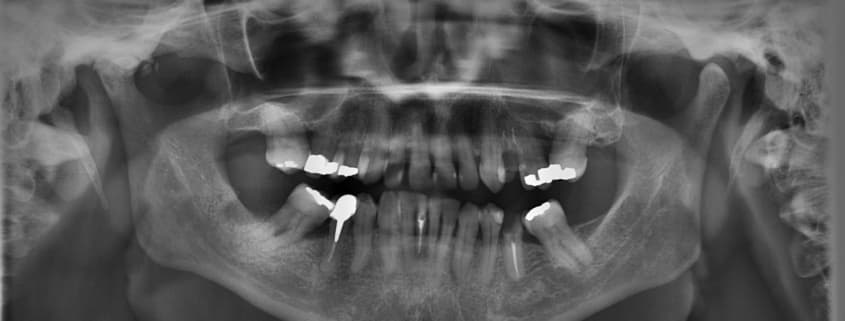

Zahnfüllung: Amalgam bleibt im Fokus der Kritik

Seit langem diskutiert man EU-weit darüber, wie man neue Regelungen im Umgang mit Amalgam als Zahnfüllstoff finden kann. Amalgam ist nach wie vor im Fokus der Kritik. Klar ist dabei, dass die Verwendung von Amalgam reduziert werden soll. Eine Entscheidung gab es bereits. Seit 2018 dürfen Zahnärzte im Bereich der EU bei drei Patientengruppen nur noch bei gerechtfertigten Ausnahmen Amalgam verwenden. Es geht um Schwangere, stillende Mütter und Kinder. Den Gegnern von Amalgam hat diese Nachricht selbstverständlich gefallen. Lange genug hatten sie für diese Regelung gekämpft. Eigentlich war sogar das totale Verbot von Amalgam das Ziel gewesen. Doch auch die Reduzierung ist bereits ein Erfolg. Im kommenden Jahr wird man prüfen, ob ein komplettes Amalgam-Verbot ab 2030 in Frage kommt.

Die geplante Prüfung eines vollständigen Verbots von Amalgam als Zahnfüllstoff basiert nicht nur auf gesundheitlichen Argumenten. Seit mehreren Jahrzehnten diskutiert man das gesundheitliche Risiko von Amalgam in Forschung und Wissenschaft. Ebenso lange steht Amalgam als Füllstoff im Fokus der Kritik. Dabei geht es um den Anteil von Quecksilber im Amalgam. Dieses Quecksilber ist potenziell zwar giftig. Doch an diesem Problem hat die Forschung beständig gearbeitet. Inzwischen setzt das heutzutage verwendete Amalgam als Zahnfüllstoff so gut wie kein Quecksilber mehr frei. Dennoch bleiben Argumente, die gegen eine Verwendung von Amalgam sprechen. Und dabei geht es nicht nur um die eingeschränkte Einsatzmöglichkeit aus optischen Gründen. Immerhin ist es nicht angemessen, Amalgam aus ästhetischen Gründen bei Frontzähnen einzusetzen.